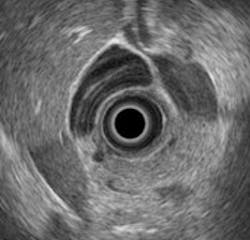

An assistant professor of physics at Kettering University (Flint, MI, USA) is seeking a better way to diagnose between chronic pancreatitis and pancreatic cancer by analyzing endoscopic ultrasound images.

Kumon and his collaborators, however, are working to quantitatively analyze the radio frequency data that underlies the ultrasound images to try to distinguish malignant from benign tissue states.

His studies to date show that a spectral analysis of the backscattered signals obtained by using electronic array echoendoscopes can provide a noninvasive method to quantitatively discriminate between chronic pancreatitis and pancreatic cancer.